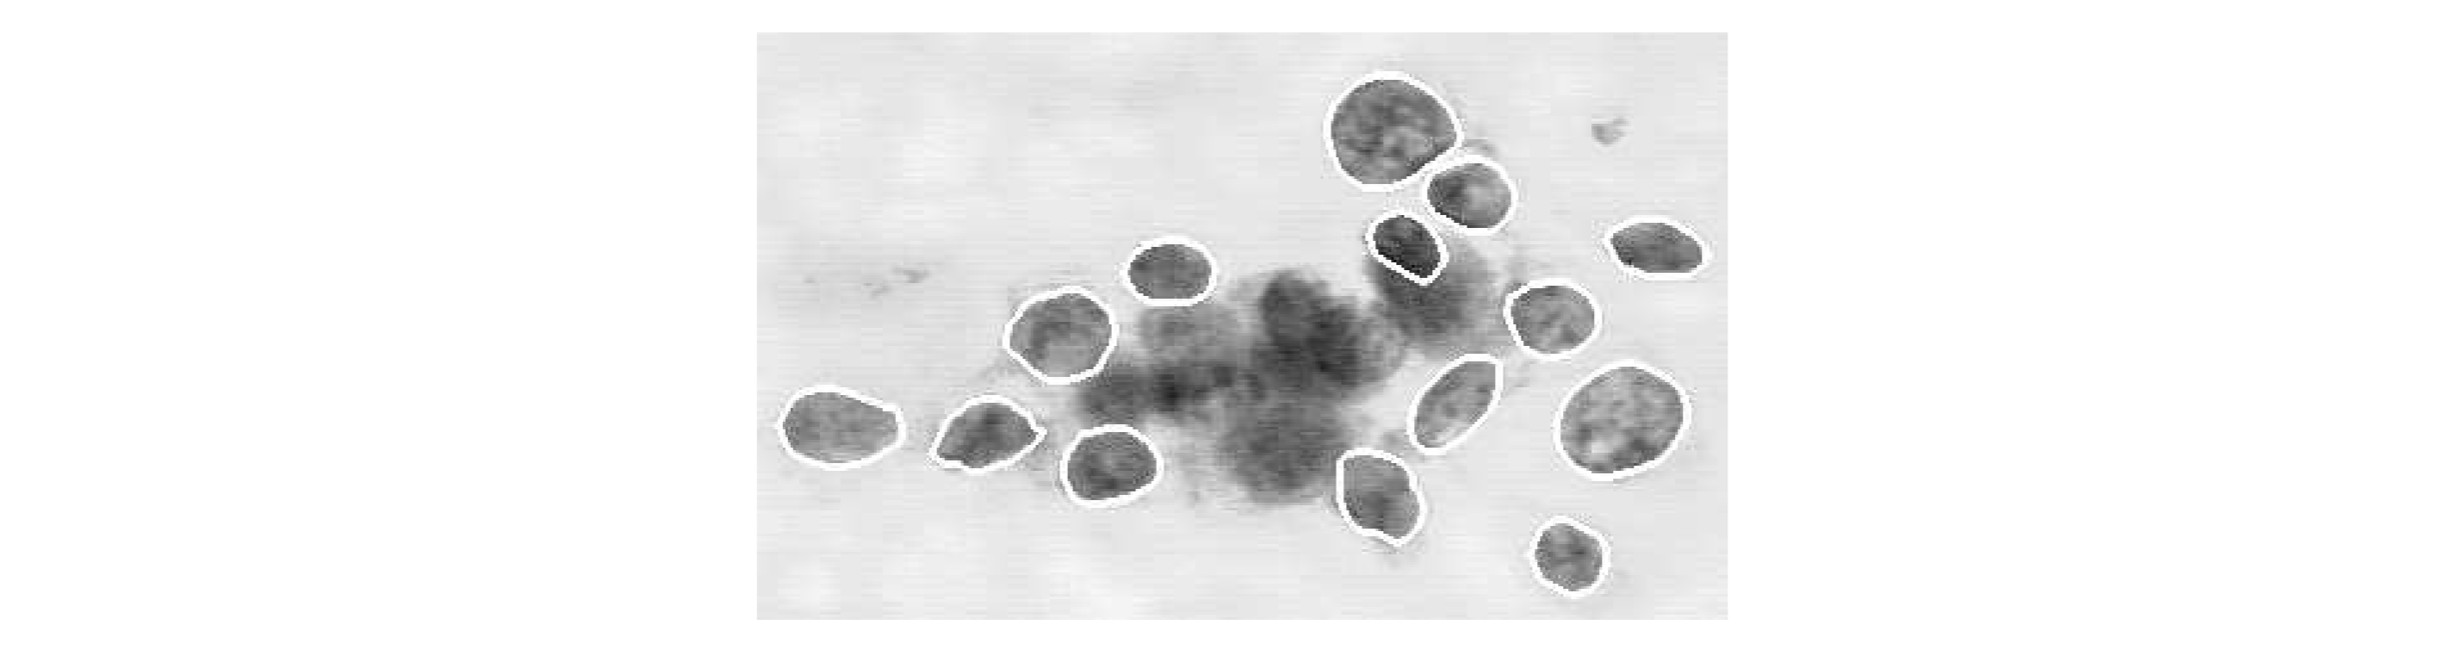

En aquest exercici, treballarem amb un conjunt de dades del món real que conté informació recollida a partir d'imatges microscòpiques de tumors de càncer de mama, similar a la imatge següent.

Cada tumor s'ha etiquetat com a benigne (no cancerós) o maligne (cancerós).